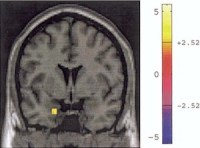

The research on structural aspects of the brain also has demonstrated key differences in the brain of borderline personality sufferers when compared to normal people. One recent study by Silbersweig, et. al. (2007) examined impulse control in people with borderline personality disorder using functional magnetic resonance imaging technology. In order to assess impulse control the researchers asked subjects not to push a button when negative words were displayed. Normal subjects showed increased activity in the areas of the brain associated with emotional regulation and inhibition of limbic regions including the amygdala (orbitofrontal and cigulate cortices). These increases did not occur in people who suffered from borderline personality disorder. Also those with borderline personality disorder demonstrated increased activity in areas of the brain (dorsal anterior cingulated cortex) related to detection of conflict related to deciding on a response, suggesting that while they were unable to exercise impulse control, they had some awareness of the conflict inherent in the experimental situation. The research leads us to

…infer that when individuals with borderline personality disorder display decreased impulse control, this loss of impulse control may reflect a deficit in recruitment of brain mechanism of emotional regulation, and this process may be potentiated by context. Particularly stressful or negative contexts could lead to more impaired impulse control (Siegle, 2007, p. 1778).